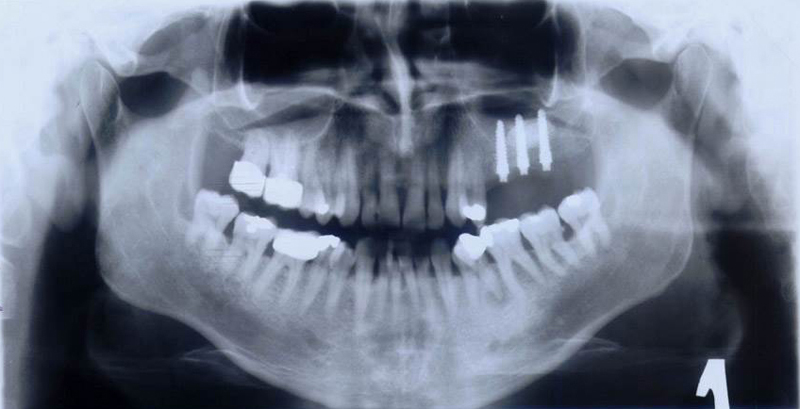

Při ztrátě molárů a premolárů v horní čelisti a jejich náhradě implantáty se často setkáváme s nedostatečnou vertikální nabídkou kosti pod čelistní dutinou, často doprovázenou i nedostatečnou horizontální nabídkou a sníženou kvalitou kosti

(v oblasti 2. premoláru v 50%, v oblasti moláru až v 80% případů nedostatečná kostní nabídka)